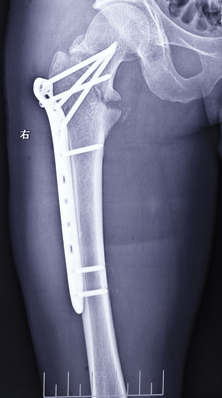

光片提示:该患者发生发生股骨颈基底部移位骨折。急诊:静脉滴注消炎。两天后对患者进行了复位内固定手术。

股骨颈骨折可发生于老年壮年青年等不同年龄段。老年人由于骨质疏松、骨强度下降,和股骨颈上区滋养血管孔密布,使股骨颈生物力学结构削弱,股骨颈脆弱。加之老年人髋周肌退化,反应迟钝,因此在不需要多大外力的作用下,如平地滑倒、由床上或车上跌下或下肢突然扭转,甚至在无明显外伤的情况下都可能发生骨折。而青壮年股骨颈骨折,往往由于如车祸或高处跌落等突然的暴力致伤。或者由于长期疲劳而致骨质劳损造成骨折。 在发生股骨颈骨折时,一般采用复位内固定方法来治疗,其疗效除与骨折损伤程度,如移位程度、粉碎程度和血运破坏与否有关外,主要与手术中的复位、固定正确与否和术后康复情况有关。